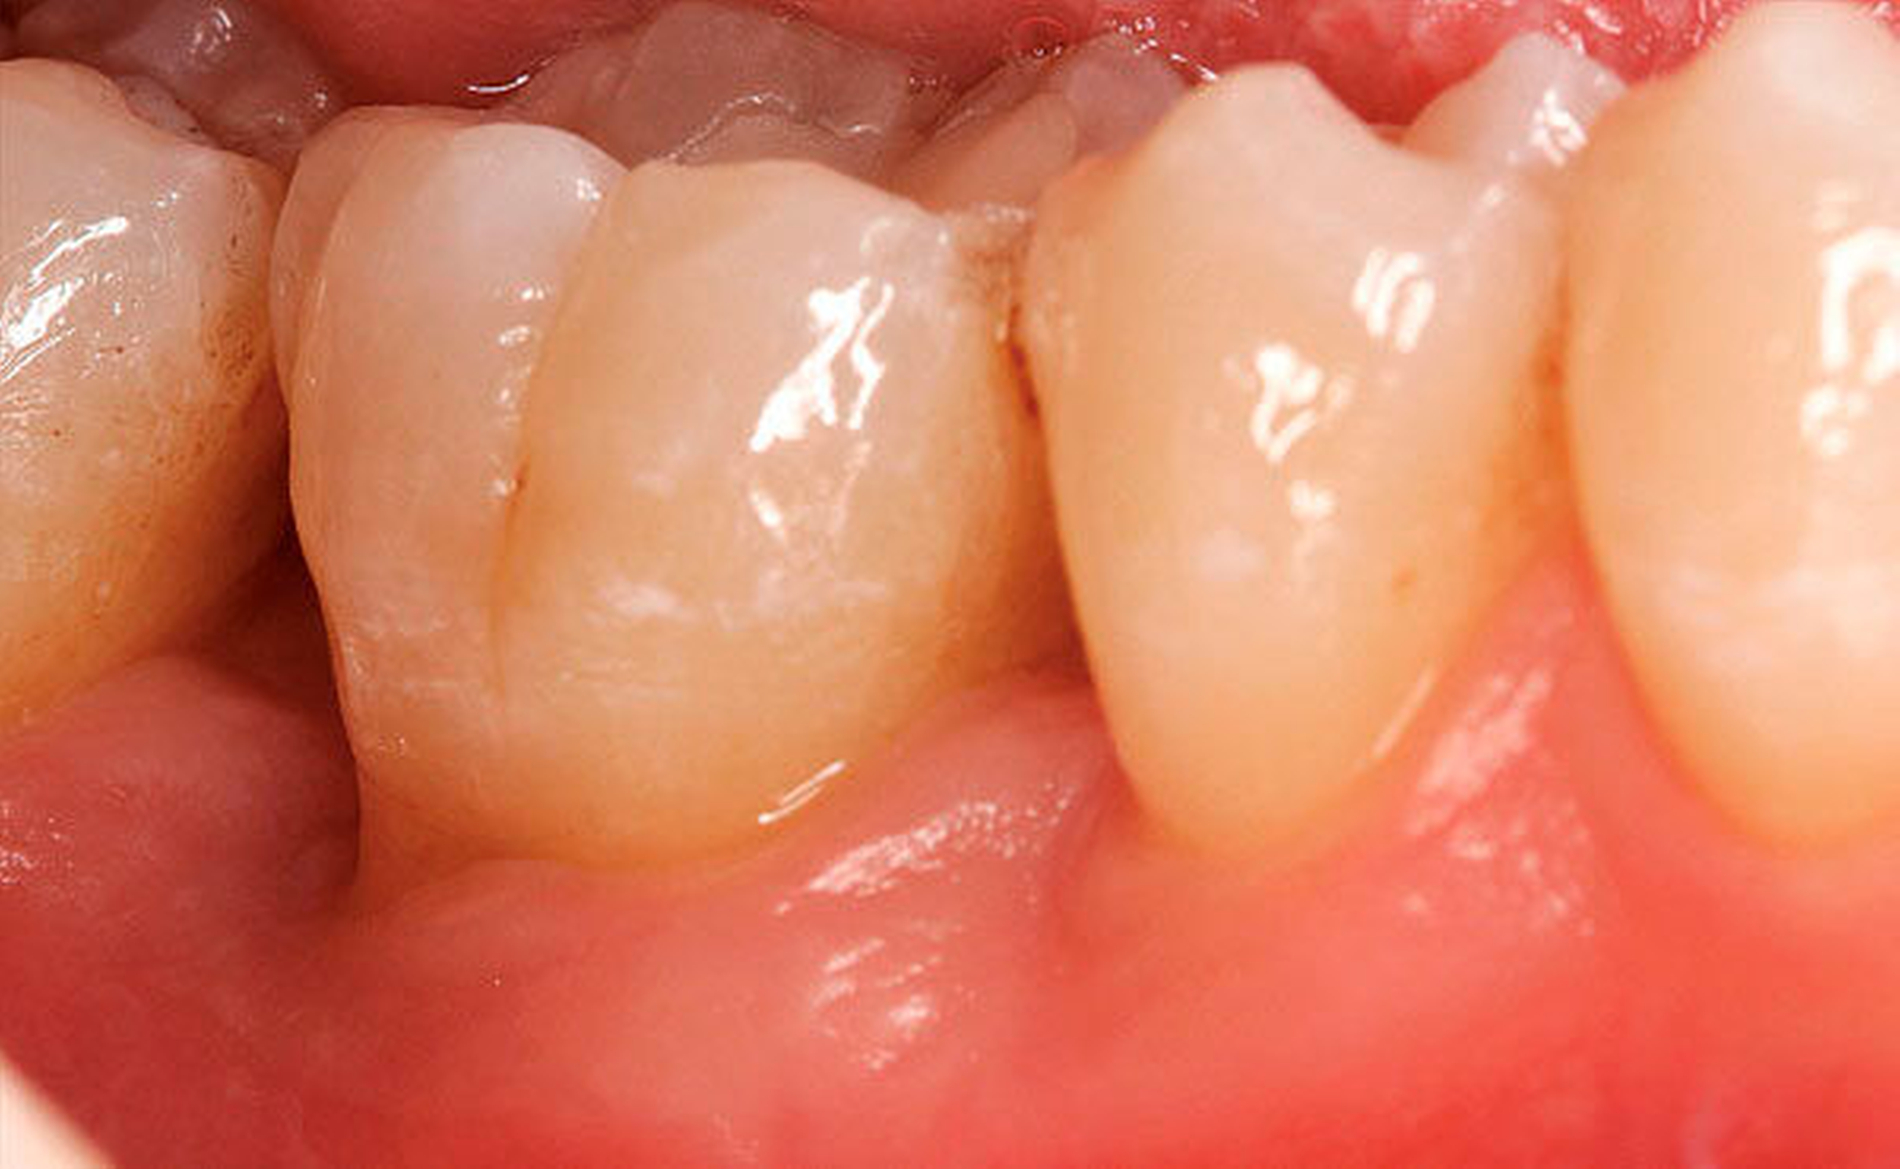

Zahnersatz- und zahnbezogene Faktoren

Dieser Abschnitt wird in der neuen Klassifikation erweitert. Er umfasst alle Faktoren, die Biofilm-bedingte gingivale Erkrankungen / Parodontitis modifizieren oder dafür prädisponieren.

- Eine Verletzung des suprakrestalen Bindegewebes durch die Restaurationsränder ist mit einer Entzündung und dem Verlust von parodontalem Stützgewebe verbunden.

- Das Design, die Herstellung, die Eingliederung und die Materialien, die für zahngetragene Restaurationen und Maßnahmen für festen Zahnersatz verwendet werden, können mit Plaqueanlagerung, gingivaler Rezession und Verlust von parodontalem Stützgewebe verbunden sein.

- Anatomische Faktoren des Zahnes (zum Beispiel zervikale Schmelzprojektionen, Schmelzperlen, Entwicklungsrillen), enger Wurzelabstand, Anomalien und Frakturen sowie die Beziehungen der Zähne im Zahnbogen stehen im Zusammenhang mit gingivaler Entzündung, verursacht durch den dentalen Plaque-Biofilm und den Verlust von parodontaler Stützgewebe.